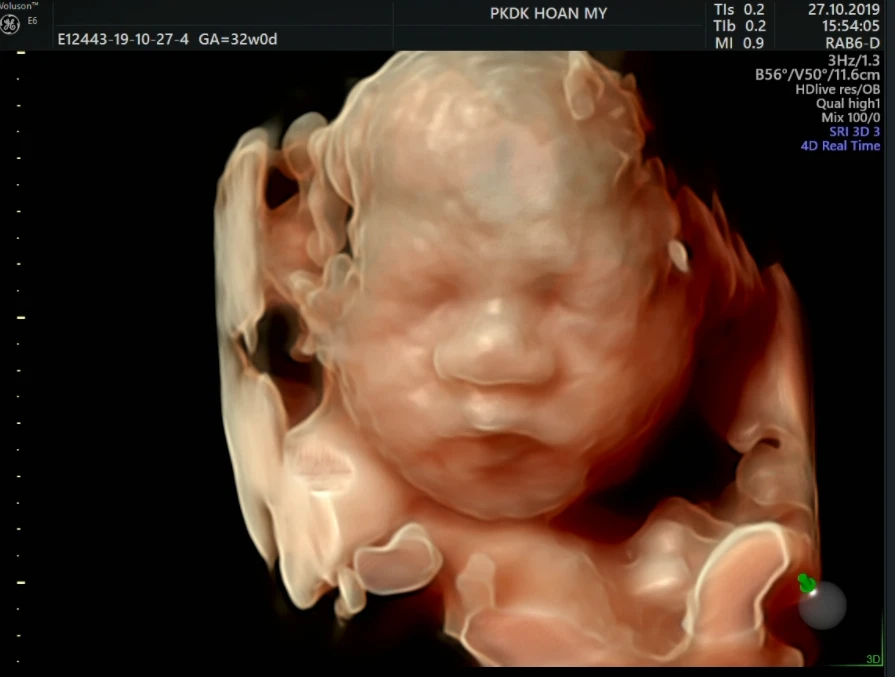

Ngược lại, siêu âm 4D, thường được tiến hành từ tuần 24 đến 32 thai kỳ, nổi bật với khả năng tạo ra hình ảnh trong không gian ba chiều và cho phép quan sát chuyển động của em bé trong bụng mẹ theo thời gian thực. Điều này không chỉ đem lại trải nghiệm thú vị mà còn giúp các bậc phụ huynh nhìn thấy cử động, như là những cái nhăn nhó, cười, hay mút tay của con yêu, tạo ra sự kết nối tình cảm đặc biệt với thai nhi trước khi bé chào đời.

Điểm khác biệt lớn nhất giữa hai loại siêu âm này chính là mục tiêu và khả năng cung cấp thông tin chi tiết. Trong khi siêu âm hình thái nhấn mạnh vào khía cạnh y tế, giúp phát hiện và xử lý các dị tật bẩm sinh, thì siêu âm 4D lại tập trung vào việc tạo ra trải nghiệm trực quan, rõ nét cho cha mẹ. Do đó, lựa chọn giữa hai loại này thường phụ thuộc vào nhu cầu và hoàn cảnh cụ thể của từng thai kỳ cũng như lời khuyên từ các bác sĩ chuyên khoa.

Cả hai phương pháp đều có vai trò đặc biệt và quan trọng trong việc theo dõi sự phát triển của thai nhi. Việc kết hợp đúng đắn giữa siêu âm hình thái và 4D giúp các bậc phụ huynh không những đảm bảo sức khỏe của con từ trong bụng mẹ mà còn mang lại những khoảnh khắc đáng nhớ trong hành trình chào đón bé yêu.